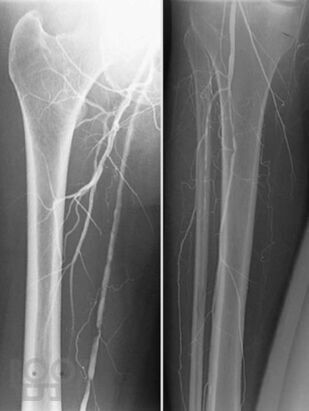

В атласе представлены более 1200 цветных иллюстраций по всем основным патологическим процессам, с которыми можно встретиться на практике, а также при изучении курса патологии или при подготовке к квалификационному экзамену по медицинским специальностям, проводимому в США (USMLE). Принцип построения атласа соответствует главам 7-го издания руководства «Основы патологии болезней Роббинса и Котрана» (Robbins and Cotran Pathologic Basis of Disease). Иллюстрации данного атласа дополняют рисунки, представленные в этом руководстве. В атлас включены иллюстрации наиболее важных рентгенологических изменений, которые отражают реальные клинические проявления при конкретных заболеваниях. Высококачественные иллюстрации имеют маркировку для определения ключевых признаков патологических изменений. В каждом наблюдении представлено комплексное описание ключевых морфологических признаков, а также клинико-лабораторные данные по наиболее важным разделам патологии. Картины макроскопических и микроскопических изменений дополнены цветными рисунками и схемами, а также соответствующими рентгенограммами. Атлас является прекрасным изданием, содержащим необходимый объём сведений или справочных материалов для читателя, имеющего различный уровень подготовки, — студента, врача, научного работника.